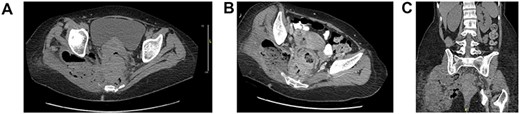

She did well postoperatively. Further metastatic workup was negative. Pathology was remarkable for invasive rectal SCC with focal basaloid features (Fig. 2). She was then referred to oncology for further management.

Histopathology invasive squamous cell carcinoma of the rectum: (A) normal anorectal junction, and squamous cell carcinoma of the rectum [Hematoxylin and eosin 4×]. (B) Squamous cell carcinoma with basaloid features with mitosis [Hematoxylin and eosin 40×]. (C) Squamous cell carcinoma with positive stain for P16 [P16 40×].